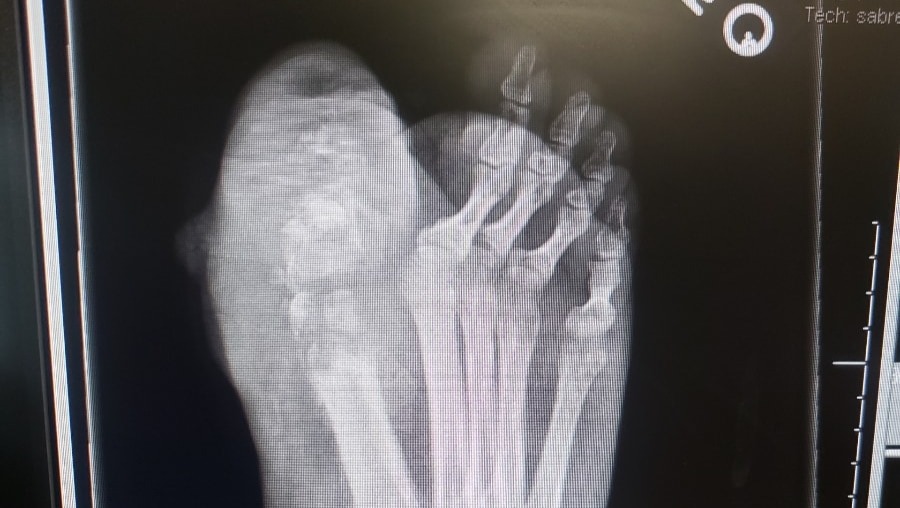

Hello everyone! My name Is Troy Jones, many of you affectionately know me as T-Bone. I recently had to check into Kaiser with a Foot infection that resulted in Osteomyelitis. It is a very dangerous inflammation and swelling of bone tissue that literally causes bone tissue to disintegrate inside your body. I stayed in the hospital for about a week and had 2 surgeries to remove what was left of my big toe on my right foot and the top of the bone right below the toe. The surgeons also had to remove much of the infection and other affect areas inside my foot and then sealed it back up with staples and stitches. Then they had to attack Osteomyelitis with a strong regiment of antibiotics. After my stay at Kaiser, I was sent home with a hard cast around my foot and told to no place and weight on it. I also had a PICC line installed in my upper right arm that goes directly to my heart that Intravenously sends antibiotics from a portable pump and I.V. bag to my PICC line. I must carry the I.V. and pump on me in a shoulder strapping bag, 24 hours a day, everyday, for up to 12 weeks if necessary. Since this whole incident began, I haven't been able to work at all doing what I love, Interpreting Sign Language for the Deaf and Hard of Hearing. This is my primary career and source of income. I have recently returned to running Karaoke at nights, but the income from that gig is limited. I am still disabled with restricted mobility, relying on a knee scooter to get around in order to keep weight bearing pressure off my casted foot.